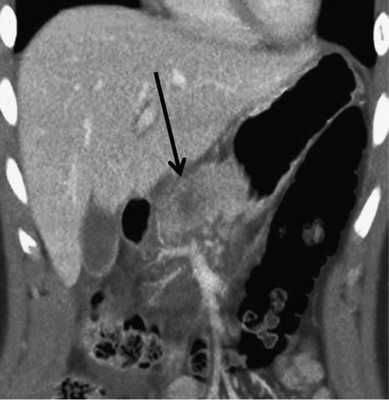

Разрывы поджелудочной железы, наблюдаемые при III (изображение. 3) и IV (изображение 4) степенях, представляют собой линейные расщелины, перпендикулярные длиннику поджелудочной железы и заполненные жидкостью или кровью (изображение 5). Если есть четкое разделение паренхимы, возможно, присутствует разрыв поджелудочной железы. Наиболее распространенным местом разрыва поджелудочной железы является тело или головка поджелудочной железы. Поверхностные образования включают менее 50 % толщины железы, в то время как разрывы включают более 50 % железы и имеют высокую частоту сопутствующих травм. Разрыв поджелудочной железы может быть пропущена или недооценен даже при МСКТ из-за наложения фрагментов разрыва.

Изображение 3. 30-летняя женщина получила травму живота во время ДТП. Изображение МСКТ показывает линейный гиподенсный участок перпендикулярно длиннику поджелудочной железы в области хвоста (белая стрелка), что указывает на разрыв хвоста III степени.